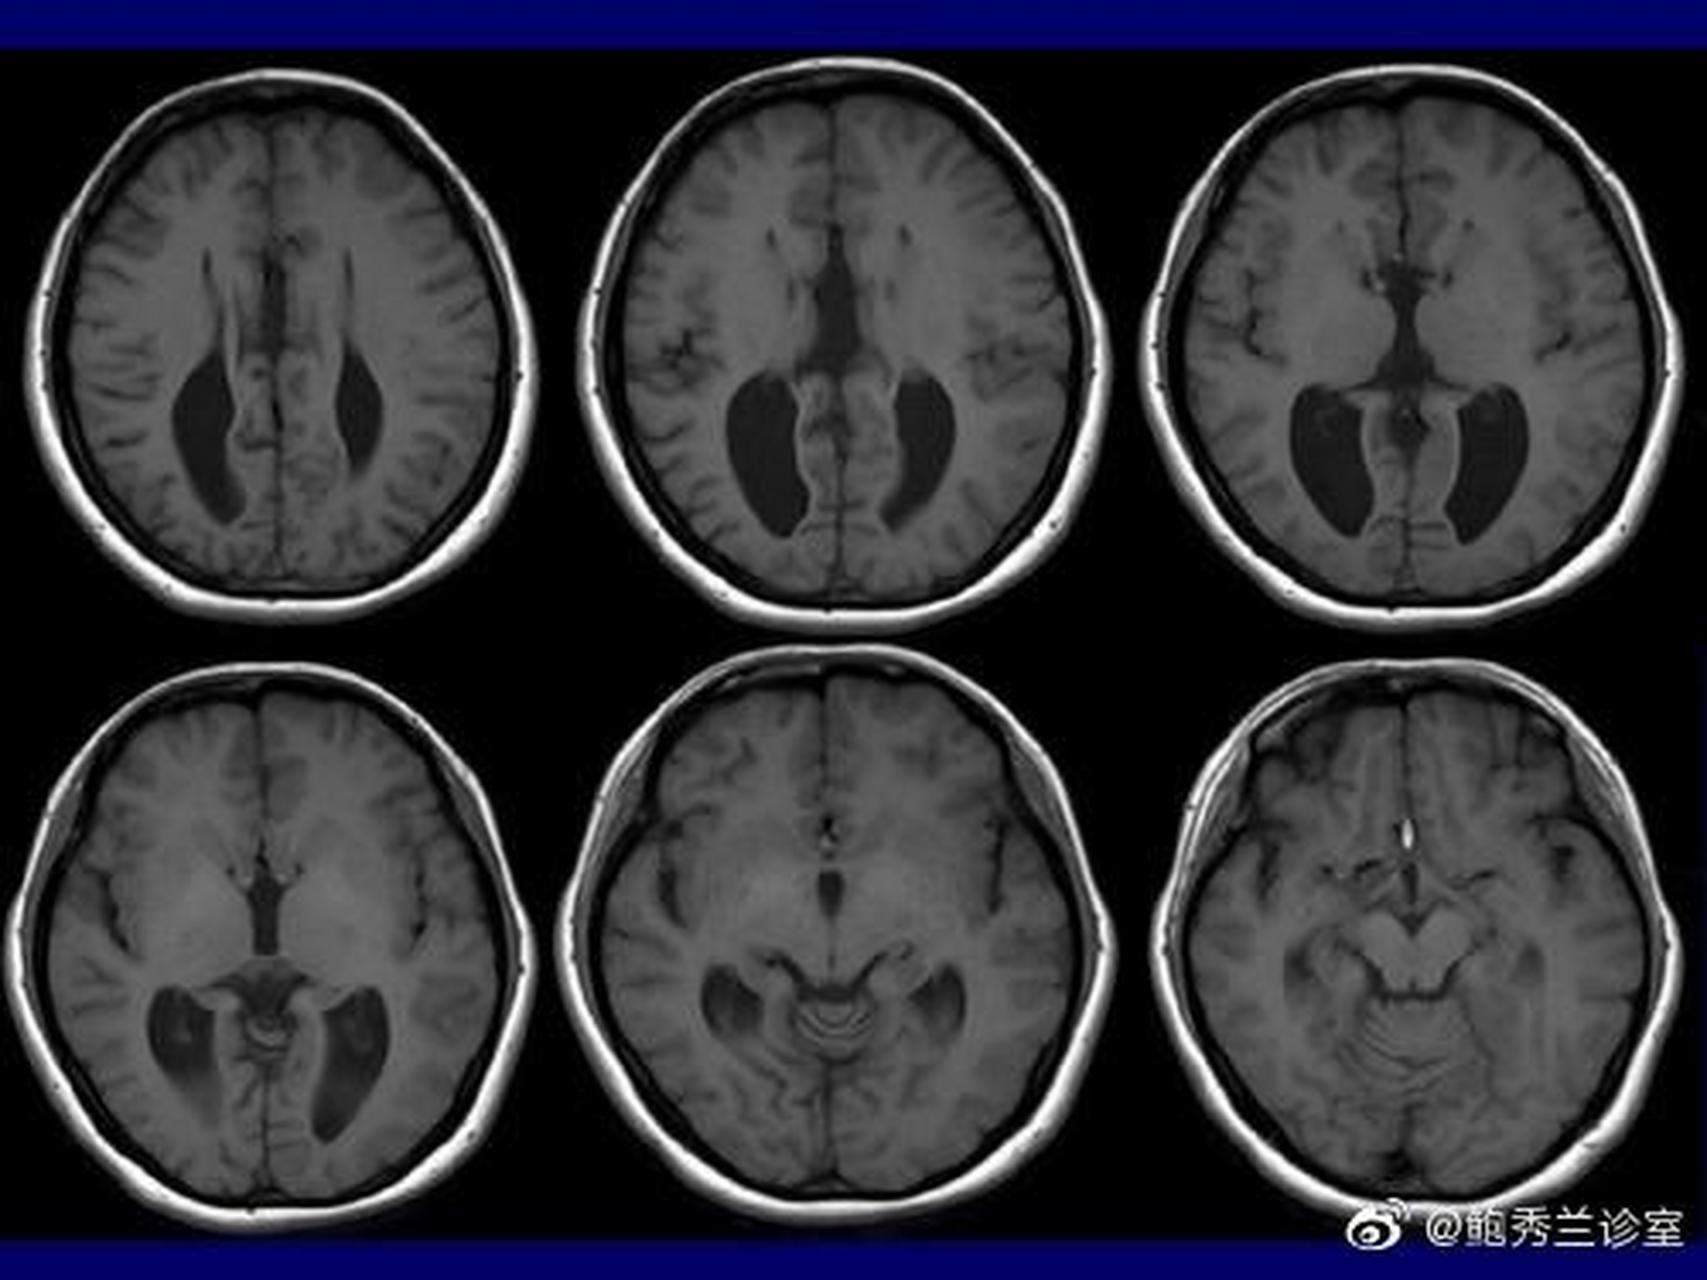

透明隔腔向后延伸形成韦氏腔,韦氏腔前方为穹窿柱,后方为胼胝体压部

做了核磁共振检查,结果显示胼胝体压部有异常,请问这是怎么回事?